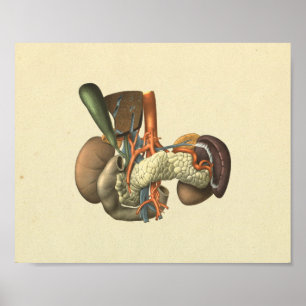

Impressão humano da anatomia dos órgãos interno

Preço15,60 €